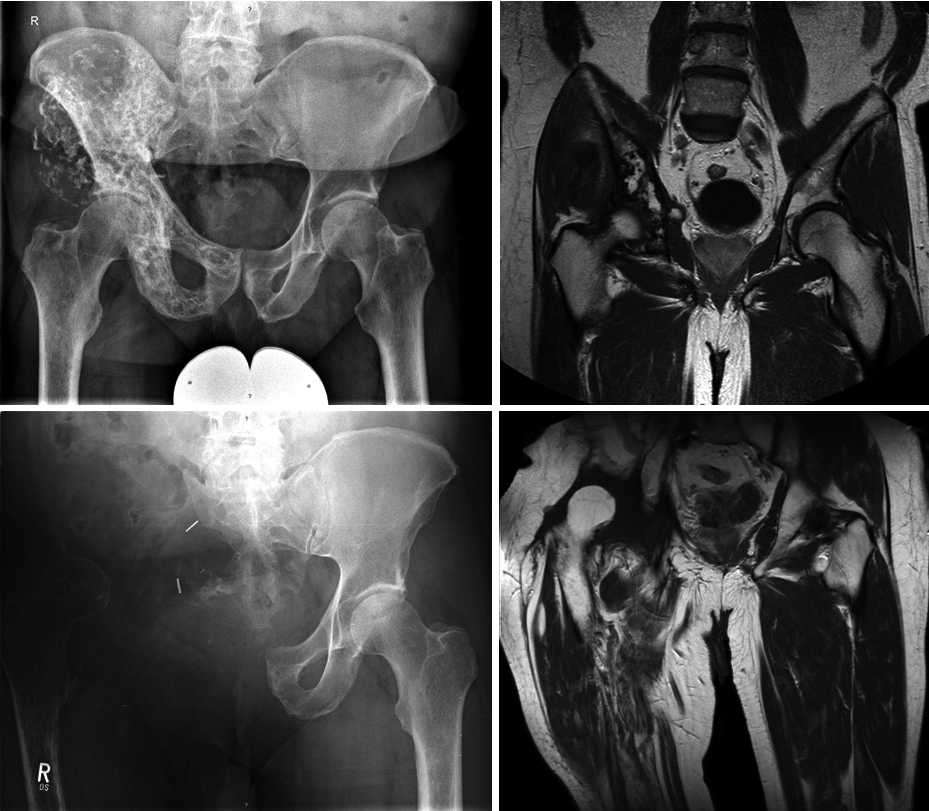

56-jähriger Mann mit Chondrosarkom (G2) des linken Beckens. Beckenteilresektion und Implantation eines großen Beckenteilersatzes mit Beckenringschluß. Bild 4 und 12 Jahre nach der OP. Gute Mobilität auch über die Jahre hinweg bei allerdings vorliegender Lockerung des Implantates am vorderen Beckenring.

Patientin, 68 Jahre, Chondrosarkom (G2), Resektion und Tumorprothese (Lumic). Eingebaut wurde hier ebenfalls ein deutlich kleinerer Beckenteilersatz, der nur noch im hinteren Becken verankert ist. 5 Jahre tumorfrei. Die Videos rechts zeigen die Mobilität 5 Jahre nach der OP mit und ohne Gehhilfe.